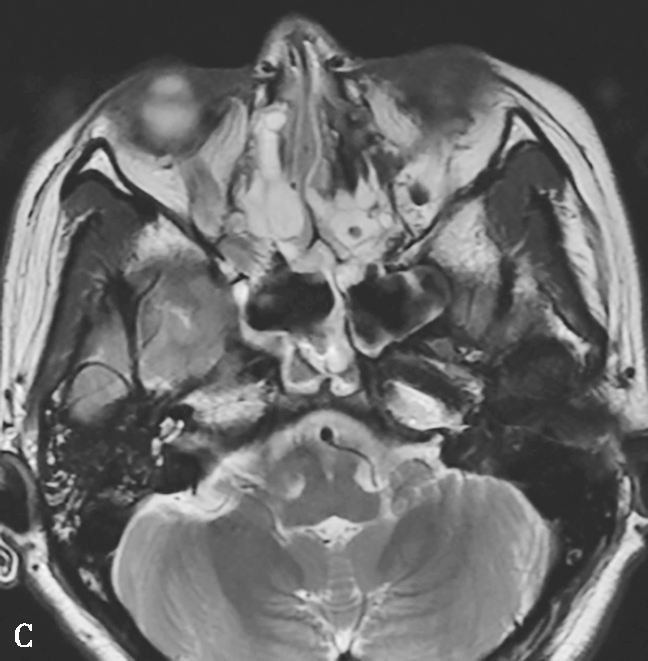

图1-3-23 急性侵袭性真菌性鼻窦炎

A、B.横断面、冠状面CT骨窗,示双侧蝶窦、后组筛窦软组织影,密度不均,窦壁骨质硬化伴局部骨质破坏,累及双侧圆孔、翼管;C~E.MRI横断面T 1 WI、T 2 WI、T 1 WI+FS+C,示双侧蝶窦、后组筛窦内混杂长T 1 、长T 2 信号,窦腔内见斑片状短T 1 、短T 2 信号影,增强扫描边缘强化,前颅底脑膜增厚强化